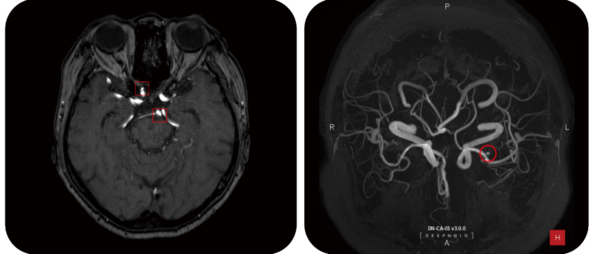

딥노이드의 딥뉴로(DEEP:NEURO) 판독화면 /딥노이드.